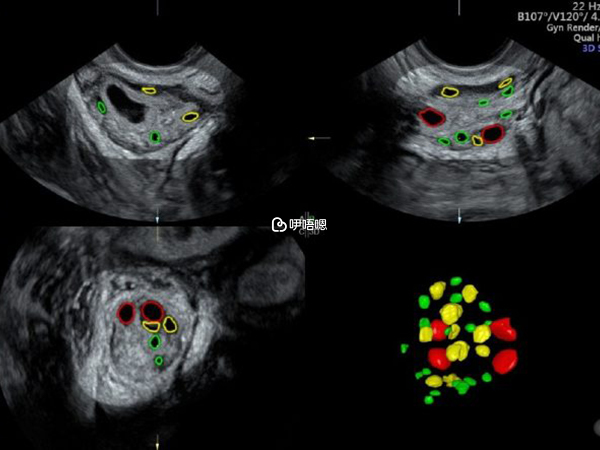

我基礎卵泡8個,屬於一般化功能,之前促排半年卵泡,有點傷身體,所以這次檢查單子當月喝中藥調理了一下,染色體半個月才會出來這個特別慢,醫生根據B超基礎卵泡和檢查單子定長方案。

長方案將調14天,當時天氣有點熱,將調期間不要大補身體和出汗,影響效果,成功之後我開始了促排,不要喝豆漿,會導致雌二醇太高降不下來,促排開始再喝,正常飲食就好,可以泡腳,這次我基礎卵泡變了11個。

我促排了7天就夜針了,後期卵泡發育不均勻,大的大小的小,是我本身之前促排半年還是有點傷身體,所以這次促排我取卵5個。